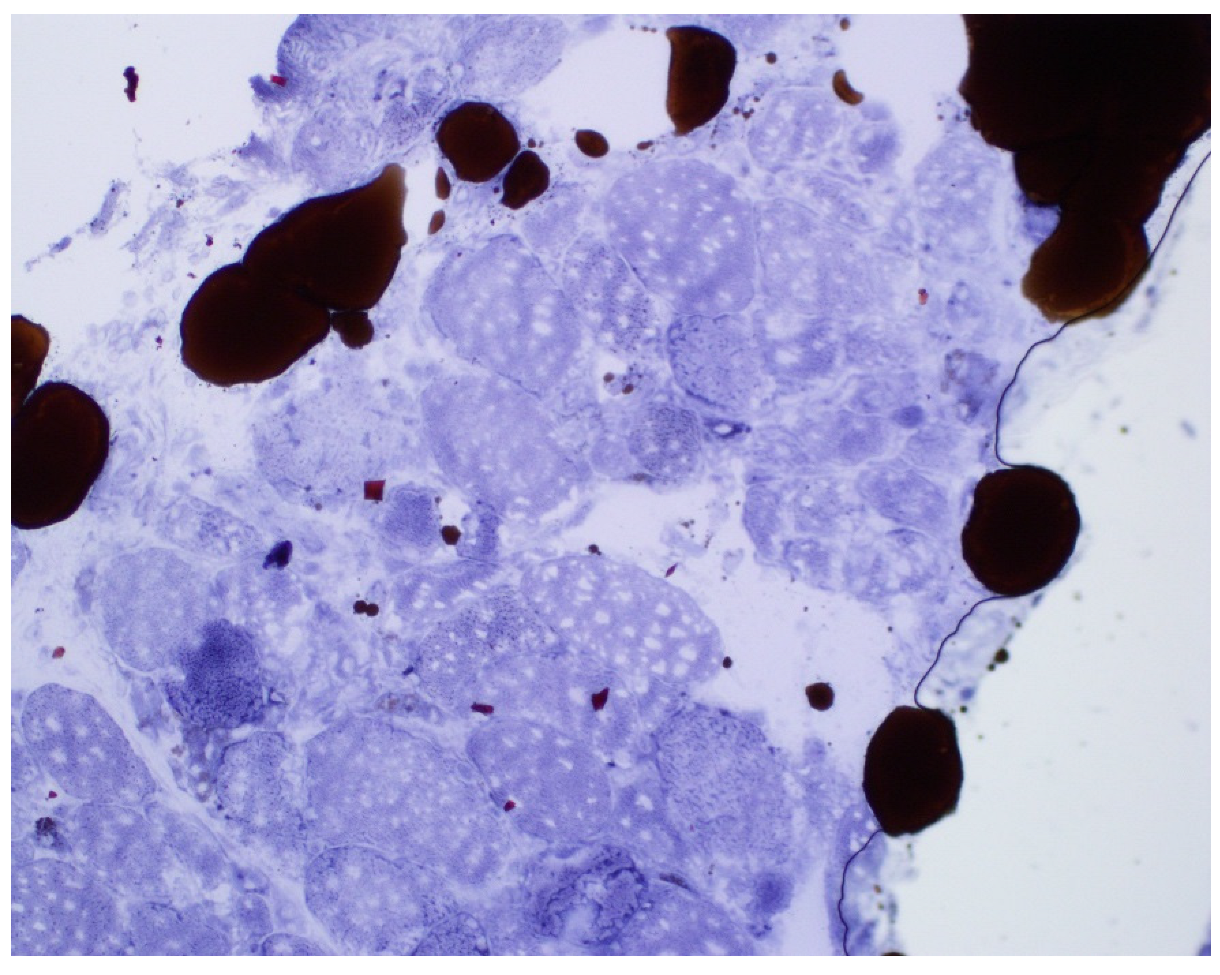

Figure 2.

Immunohistochemistry (CD 68-macrophage) foci of infiltrate.